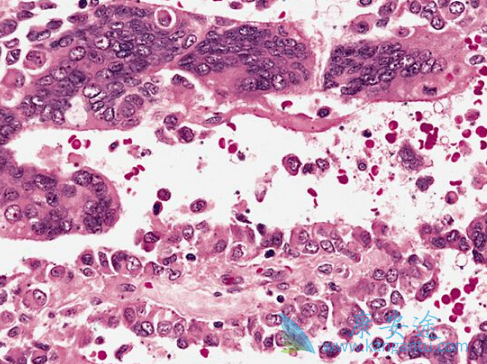

软组织肉瘤是一种发生在芥蒂组织的恶性肿瘤,可伸张在身体不同部位,恶性度高,发病年率较小,临床的治疗方法也十分有限。常见的如恶性纤维组织细胞瘤/高度恶性多形性肉瘤、脂肪肉瘤、平滑肌肉瘤、滑膜肉瘤和恶性外周神经鞘瘤都从属于软组织肉瘤。帕唑帕尼是一种多激酶抑制剂,最先获批的适应症为晚期肾癌。

不过在随后的临床试验中发现,帕唑帕尼对软组织肉瘤也有很好的疗效,故而又获批了治疗之前接受化疗的晚期软组织肉瘤(STS)的适应症。但帕唑帕尼对脂肪性STS或胃间质肿瘤疗效尚未确定。在III期临床试验(EORTC62072),368例既往蒽环类为基础的化疗治疗失败的转移性的非脂肪性STS患者分别接受帕唑替尼或安慰剂治疗,PFS显着增高,4.6:1.6月。